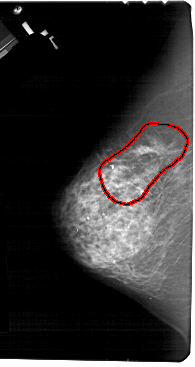

A_1510_1.LEFT_CC

LEFT_CC LINES 5491 PIXELS_PER_LINE 2911 BITS_PER_PIXEL 12 RESOLUTION 43.5 OVERLAY

FILE: A_1510_1.LEFT_CC.OVERLAY

TOTAL_ABNORMALITIES 1

ABNORMALITY 1

LESION_TYPE CALCIFICATION TYPE PLEOMORPHIC DISTRIBUTION REGIONAL

LESION_TYPE MASS SHAPE IRREGULAR MARGINS SPICULATED

ASSESSMENT 5

SUBTLETY 5

PATHOLOGY MALIGNANT

TOTAL_OUTLINES 1

BOUNDARY